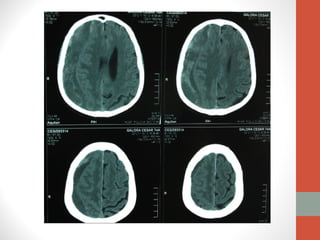

Tomografía

Simple de

Cráneo

Hematoma Subdural Crónico

• Acúmulo de sangre en el espacio subdural.

• Entre la aracnoides y la duramadre.

• Espacio virtual, fácilmente expansible, a costa de colapsar el

cerebro subyacente.

• TAC

• Mayor densidad (más blanca) que el cerebro.

• Sangre, células y otros componentes indican que es relativamente

reciente su formación

• Menor densidad (más negra) que el cerebro.

• Las células y la mayor parte de las proteínas degradadas,

correspondiéndose con un líquido amarillento hiperproteico; indican

varios meses de antelación.

• NOMURA

• NAKAGUCHI

•   Hiperdenso

•   Homogéneo

•   Isodenso

•   Laminar

•   Hipodenso

•   Separado

•   Mixto

•   Trabecular

•   Layering